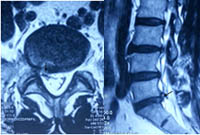

术前可见椎管内脱出的巨大髓核组织压迫神经(箭头所示) 术后3月复查MRI显示脱出的髓核组织消失,神经无明显受压